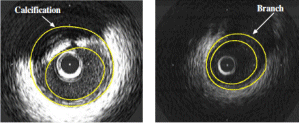

Medical image analysis. We developed fully automated techniques for the detection of the lumen and media-adventitia borders in Intravascular Ultrasound (IVUS) images. Intensity information, as well as the result of texture analysis, generated by means of a multilevel Discrete Wavelet Frames decomposition, are used in two different techniques for contour initialization. For subsequently producing smooth contours, three techniques based on low-pass filtering and Radial Basis Functions are introduced. [ubm08]